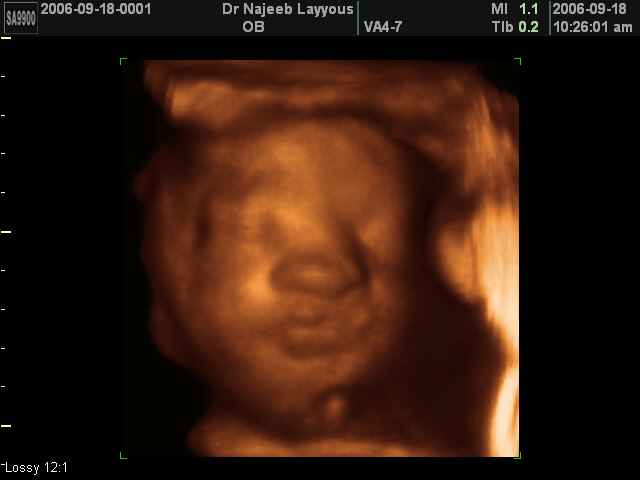

- صور لوجه الجنين في داخل الرحم

- صور لتصرفات الجنين داخل الرحم

صور لتصرفات الجنين داخل الرحم بجهاز الالتراساوند ثلاثي الأبعاد | الدكتور نجيب ليوس